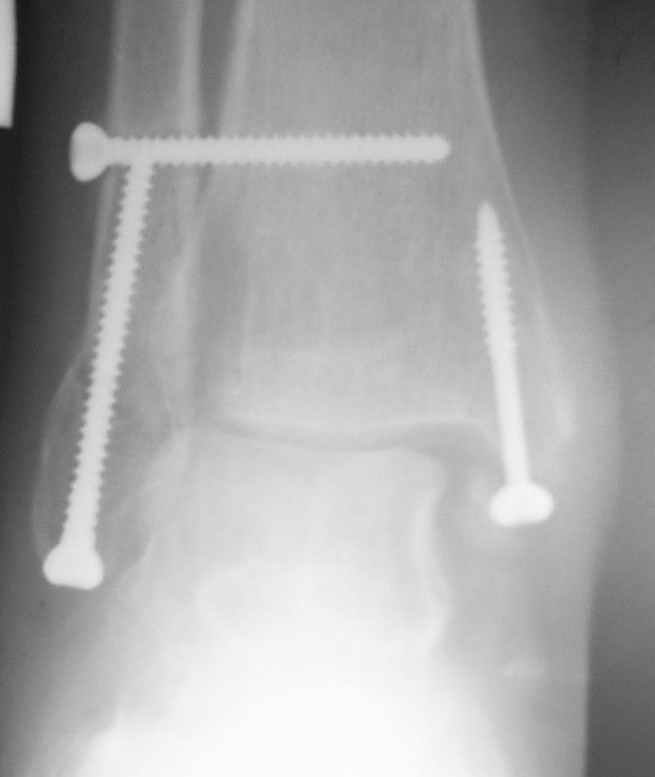

Операция 29 июля